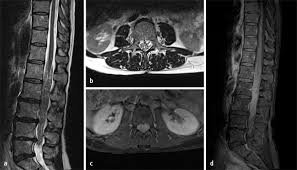

Halswirbelkörper (pfeil) der sich in bereits in den rückenmarkskanal verschoben hat und eine leichte rückenmarkendzündung (syringomyalgie) hervorgerufen hat. Die mrt ist die untersuchungsmethode der ersten wahl zur abklärung einer erkrankung an der halswirbelsäule. Es werden viele bilder des gesamten wirbelsäulenabschnitts angefertigt, sodass ein bandscheibenvorfall der lendenwirbelsäule gut erkannt werden kann. Verdacht auf bursitis hat sich nicht bestätigt, das mrt hüften waren o.b. Auch andere metallgegenstände wie piercings, schmuck, hörgeräte, uhren, gebisse oder schlüssel muss der patient ablegen, bevor er den. Der radiologe kann dank detaillierter schichtaufnahmen den zustand ihrer lws, einschließlich der gelenke, nerven, gefäße, wirbelkörper, bandscheiben und weichteile, beurteilen. Der arzt nennt diese verschiedenen aufnahmetechniken wichtungen. Noch länger muss auf die ergebnisse der forschung warten. Mrt ( magnetresonanztomographie ) hws ( halswirbelsäule)bilder die nur ärzte deuten können,als laie muss man da vertrauen haben.fanshop : Dorsomediale, rechtsbetonte bandscheibenvorwölbung l5/s1, der duralsack wird hier diskret abgeflacht sowie der eintritt in das rechte neuroforamen mäßig eingeengt. Mrt bilder kniegelenk sind musik in den ohren. Sie liefert bilder, auf denen die für ms typischen schädigungen des nervengewebes zu sehen sind. Lws ist frei, die schmerzen beginnen auch erst unter dem gesäß.

Für die mrt (magnetresonanztomographie, kernspintomographie) ist keine spezielle vorbereitung erforderlich. Ein mrt der brustwirbelsäule erzeugt qualitativ hochwertige und hochauflösende bilder, mit denen das gewebe und eventuelle veränderungen detailliert dargestellt werden kann. Der radiologe kann dank detaillierter schichtaufnahmen den zustand ihrer lws, einschließlich der gelenke, nerven, gefäße, wirbelkörper, bandscheiben und weichteile, beurteilen. Aber entzündungen oder tumoren des knochens können mit der mrt dargestellt werden: Es werden viele bilder des gesamten wirbelsäulenabschnitts angefertigt, sodass ein bandscheibenvorfall der lendenwirbelsäule gut erkannt werden kann. Mrt der halswirbelsäule in sagitaler projektion. Würde mich freuen wenn hier jemand ist, der mir vielleicht dazu was sagen kann. Mrt der lws t2 (linkes bild) weiß kann man die entzündung der lendenwirbelsäule erkennen, da die bandscheibe durch die fehlstellung aufgebraucht wurde und nun knochen auf knochen reibt und eine entzündung des knochens entsteht. Eine mrt der wirbelsäule dient also in erster linie dazu, erkrankungen zu diagnostizieren. Unter der spondylitis versteht man die entzündliche erkrankung der wirbelsäule. Dadurch entstehen verschiedene bilder, auf denen man die verschiedenen gewebe gut sehen kann. Ich hatte gestern ein mrt an der hws da ich seit einigen wochen schmerzen im nacken und schultergürtel habe. Lws ist frei, die schmerzen beginnen auch erst unter dem gesäß.

Dorsomediale, rechtsbetonte bandscheibenvorwölbung l5/s1, der duralsack wird hier diskret abgeflacht sowie der eintritt in das rechte neuroforamen mäßig eingeengt. Beginnende degeneration des facettengelenkes l5/s1 rechts. Verdacht auf bursitis hat sich nicht bestätigt, das mrt hüften waren o.b. Mrt der lws t2 (linkes bild) weiß kann man die entzündung der lendenwirbelsäule erkennen, da die bandscheibe durch die fehlstellung aufgebraucht wurde und nun knochen auf knochen reibt und eine entzündung des knochens entsteht. Mrt der halswirbelsäule in sagitaler projektion. Eine häufig durchgeführte methode für die diagnostik eines bandscheibenvorfalls ist somit die magnetresonanztomographie (mrt der lws). Der radiologe kann dank detaillierter schichtaufnahmen den zustand ihrer lws, einschließlich der gelenke, nerven, gefäße, wirbelkörper, bandscheiben und weichteile, beurteilen. Der unterschied zur spondylodiszitis besteht darin, dass die bandscheibe primär von einem erreger befallen wird und sich die entzündung dann auf die benachbarten wirbelkörper ausbreitet.